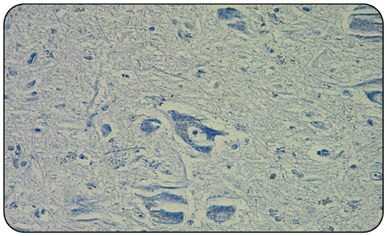

Obtained results indicate that the 2/2 positive controls (goat and sheep) (Figure 2), always presented the red granular immunoprecipitate, in addition to vacuoles that indicate the presence of the prion associated with scrapie, and that agrees with the described by other authors.1,10 Unlike the 2/2 negative controls and all 50/50 samples of national goats obex (Figure 3), in which immuno precipítate was not observed, nor were vacuoles or spongioses of nervous tissue. This confirms that 100% of the analyzed samples are negative to classic scrapie (Table 2).

Figure 3 Microphotography of a goat obex negative control (IHC 400x). In which normal morphology of the nervous tissue and neuronal sums is observed. No vacuoles or the presence of immunostaining of red granular precipitate are observed.